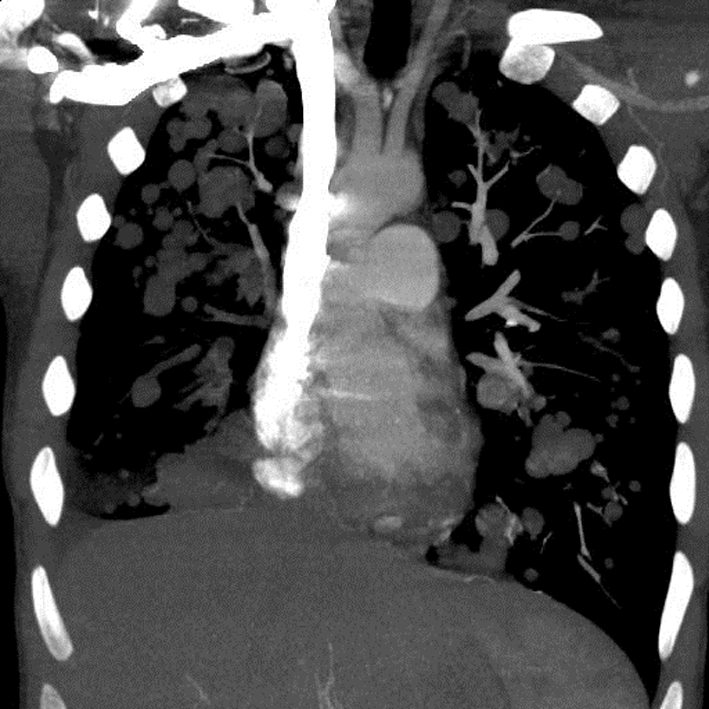

A chest X-ray (Fig. 1) was obtained and showed the presence of multifocal rounded airspace opacities within both lungs. Subsequently, a CT scan of the chest (Fig. 2, 3) was obtained which demonstrated bilateral pulmonary emboli along with bilateral conglomerate pulmonary nodules in both lower lungs.

![]() Click for large image | Figure 3. Coronal section of CT chest showing bilateral cannonball pulmonary nodules. |

Based on patient’s history of IV drug abuse, recent episode of cellulitis, concomitant lower back pain and consistent imaging findings, the diagnosis of right-sided infective endocarditis with septic pulmonary embolism was initially considered and patient was empirically started on IV antibiotics after drawing blood cultures. However, a transthoracic echocardiogram obtained the next day did not reveal any vegetations and the patient continued to remain afebrile with all blood cultures coming back negative. This prompted a reconsideration of the diagnosis. All radiographic images were reviewed again with radiology and were notable for the lack of necrosis in the pulmonary nodules. A follow-up abdominal CT also revealed the presence of retroperitoneal lymphadenopathy indicating a possible neoplastic process.

In rare cases, patients may present with symptoms from the metastasis. In these patients, a careful physical examination is of prime importance in pointing towards the correct diagnosis. Radiological features such as multiple lung nodules greater than 1 cm in size seen on a plain chest radiograph are also usually indicative of disseminated malignancy to the lungs [5, 6]. Such large, rounded “cannonball” nodules are associated with poor prognosis [7, 8].